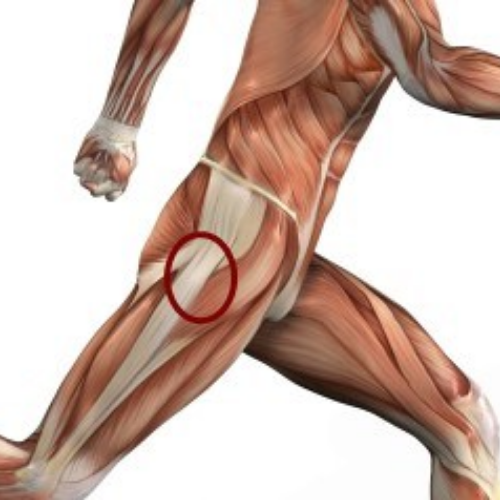

Hip pain can arise from a range of causes including overuse, arthritis, trauma, or tendon and muscle injuries. Because the hip joint supports most of your body’s weight, even minor issues can lead to persistent discomfort and stiffness. At REGENIQUE, we focus on understanding the exact cause of your hip pain—whether it's from the joint, surrounding soft tissues, or referred nerve pain—so your treatment is accurate and effective.

Lateral Hip Pain - Greater Trochanteric Pain Syndrome

Sports Related Hip Pain